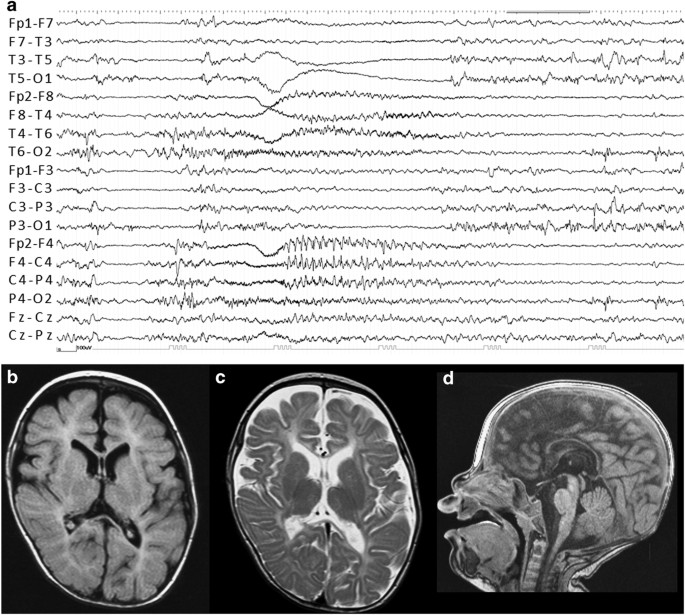

Migrating Focal Seizures In Autosomal Dominant Sleep Related Hypermotor Epilepsy With Kcnt1 Mutation Seizure European Journal Of Epilepsy